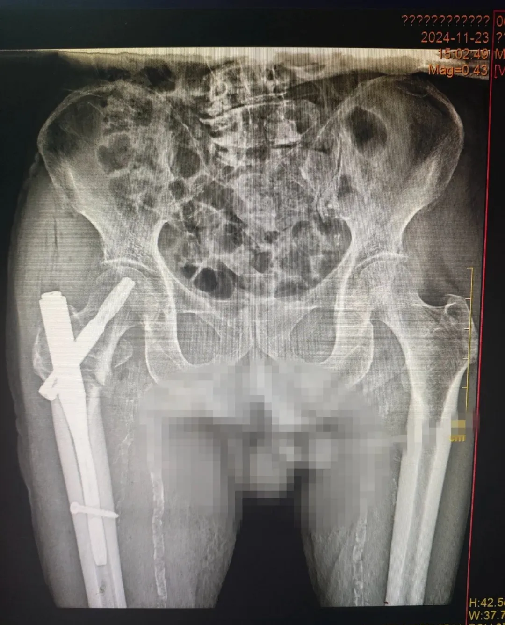

近日,醫(yī)院成功為97歲高齡患者實施右股(gǔ)骨粗隆間骨折閉合複位(wèi)髓內釘內固定術(PFNA)。

患者餘(yú)某,男性,97歲高齡,因在家不慎摔傷致右股骨粗隆間骨折住院治療,入院診斷:右股骨粗隆間骨折,中度貧(pín)血,嚴重營養不良,嚴重骨質疏鬆,低鉀血症,腦梗死(sǐ)後遺症,高血壓病(bìng),慢支肺氣腫。創傷骨科在接診後,迅速為患者開通“高(gāo)齡骨折綠色生(shēng)命通道”,組織心血(xuè)管(guǎn)內科、呼吸內(nèi)科、營養科、麻醉科等多學科會診(zhěn)後,全麵評估病情、嚴格把控圍手術期各(gè)項指標,精心(xīn)定製手(shǒu)術方案與術後風險預案,經與患者及家屬溝通同意手術後,在椎管內麻醉下行(háng)“右股骨粗隆間骨折閉合複(fù)位髓內釘(dìng)內固定術”,經多學科(kē)協作在患者入(rù)院48小時內最佳手術窗口(kǒu)期完成(chéng)手術,術後指導功能鍛煉(liàn),最大可能避免了老(lǎo)年髖部骨折如血栓,壓(yā)瘡,墜積性肺炎等致命性並(bìng)發症,患者入院治(zhì)療10天後康複出院。患者及家屬對醫院的醫療水平給予了高度的肯定,對醫護人員的辛勤付出表達了衷(zhōng)心的感謝!